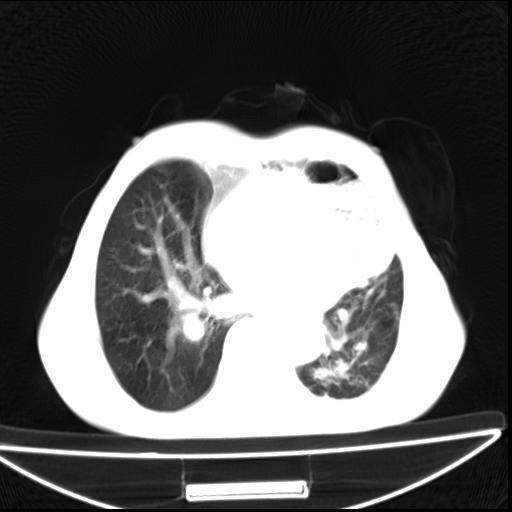

男  70岁,发烧咳嗽4天。盗汗,消瘦。无痰中带血丝,以前有肺tb病史,ct见,双肺tb,左侧胸廓塌陷,左胸膜肥厚粘连。纵隔移位,右侧胸腔积液,大家说说那个心影前左肺舌叶除了肺大炮还有炎症还是干酪性肺炎?有占位吗?我看纵隔淋巴结也大。

1)两肺继发性肺结核并左肺上叶肺不张,支气管扩张。2)双侧胸膜炎(胸膜增厚+少量胸腔积液)。

两肺继发性肺结核并感染,左肺上叶肺不张。建议ct增强。